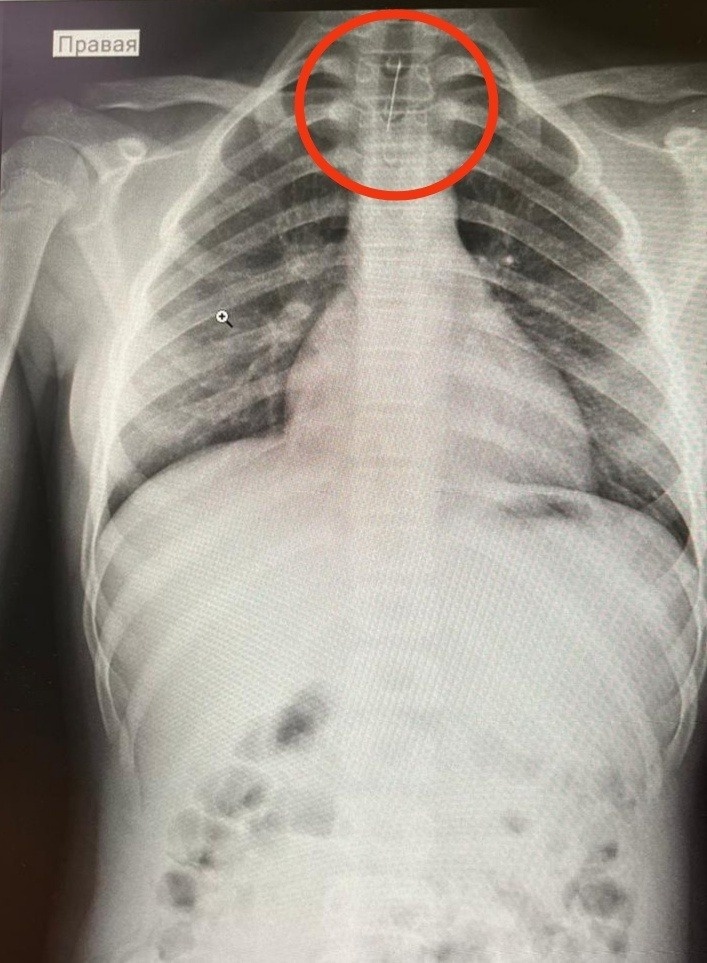

Врачи Детского научно-клинического центра имени Л. М. Рошаля в Московской области успешно извлекли иглу из глотки 15-летней девочки.

Подросток случайно проглотила иголку из любопытства, после чего почувствовала сильную боль в горле, рвоту с кровью и затруднённое глотание.

Заведующий отделением эндоскопических методов диагностики и лечения Александр Иноземцев провёл операцию без единого разреза — инородный предмет был удалён эндоскопическим путём.

Игла не успела повредить слизистую.